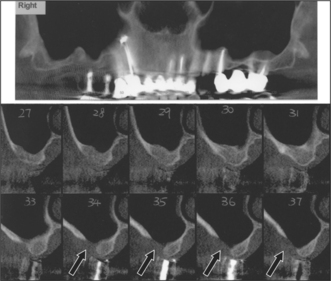

Special investigations

The height, width and overall shape of the residual ridge are evaluated from study models and radiographs to ensure adequate bone to support the implant. Articulated study casts are required to evaluate the occlusion; there should be no excessive forces on the implant during lateral or protrusive excursions of the jaws. A preliminary assessment of the ideal position and angulation of implants may be made from the study casts, in conjunction with a surgical stent (Fig. 11.19). Radiographs (Fig. 11.20) will determine the quality of the bone and help in assessing suitable sites for implants. The radiographs should adequately demonstrate important structures (the inferior alveolar neurovascular bundle, the floor of the nose, the maxillary antrum and adjacent teeth).

image

Fig. 11.20 (a) A panoramic radiograph yields much information about the teeth and jaws, but is unhelpful in determining the suitability of the bone at the proposed site of an implant in tooth 16 position. (b) A tomographic view of the bone in the tooth 16 area gives more information about the quality of the bone and the height of the maxillary sinus.

Most X-ray units do not give 1:1 magnification of the image: this must be borne in mind when planning the optimum dimensions of an implant from the radiographs. An acrylic stent may be used to determine the planned location of an implant. The stent is fitted over the teeth or edentulous jaw (Fig. 11.19) when the radiograph is taken.

CT scans (Fig. 11.22) are gaining popularity in the assessment of a patient before implant surgery. Cone-beam CT scan units offer improved functionality and convenience over conventional CT scanning units (http://www.imagingsciences.com/pro_iCAT_features.htm). In the above illustration, a patient requesting implants in the right posterior maxillary sextant has undergone an I-Cat scan to assess the bone. There is a deficiency in the buccal bone in sections 34–36, and clearly bone grafting is required before implants can be placed.

Fig. 11.22 An example of a CT scan showing a right posterior maxillary sextant with an obvious deficiency of bone (arrows), requiring augmentation with a sinus lift before implant placement.